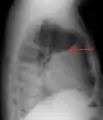

A pleural effusion appears as an area of whiteness on a standard posteroanterior chest X-ray.[7] Normally, the space between the visceral pleura and the parietal pleura cannot be seen. A pleural effusion infiltrates the space between these layers. Because the pleural effusion has a density similar to water, it can be seen on radiographs. Since the effusion has greater density than the rest of the lung, it gravitates towards the lower portions of the pleural cavity. The pleural effusion behaves according to basic fluid dynamics, conforming to the shape of pleural space, which is determined by the lung and chest wall. If the pleural space contains both air and fluid, then an air-fluid level that is horizontal will be present, instead of conforming to the lung space.[8] Chest radiographs in the lateral decubitus position (with the patient lying on the side of the pleural effusion) are more sensitive and can detect as little as 50 mL of fluid. At least 300 mL of fluid must be present before upright chest X-rays can detect a pleural effusion (e.g., blunted costophrenic angles).

A pleural effusion as seen on lateral upright chest x ray